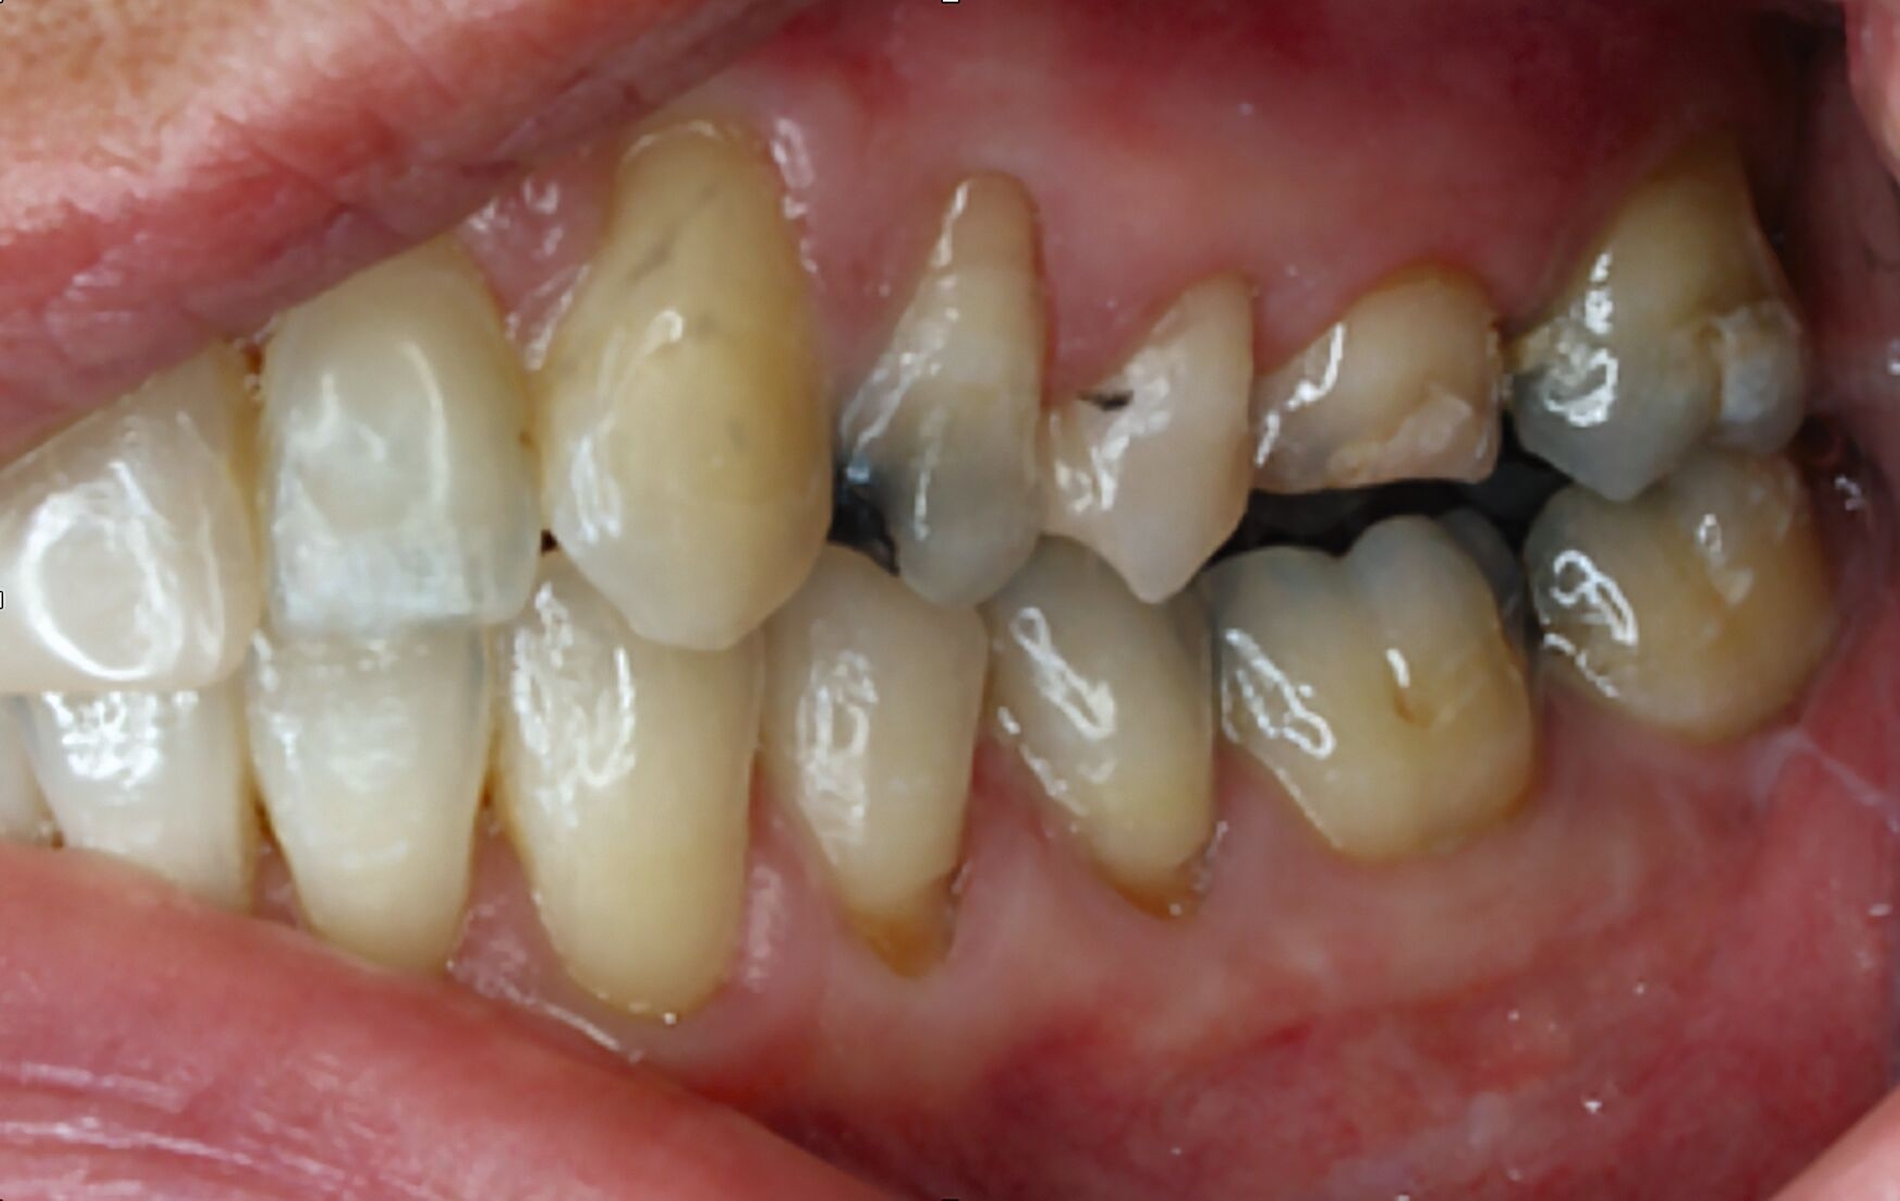

Klinisch zeigten sich diverse großflächig, mehrheitlich mit Amalgam gefüllte Seitenzähne, suffiziente endodontische Behandlungen an den Zähnen 16 und 14 sowie intakte Kronen an den Zähnen 16 und 48 (Abbildung 2). Ein Parodontaler Screening-Index (PSI) wurde erhoben (1-1-0-0-2-1), der stabile Verhältnisse nachwies. Das funktionelle CMD-Screening zeigte eine nicht-druckdolente Kaumuskulatur sowie eine uneingeschränkte Mundöffnung ohne Reiben und Knacken.

Tabelle 1 zeigt das entsprechende Befundschema mit den Taschentiefen mesial und distal, den Lockerungsgraden und den Sensibilitätsüberprüfungen mittels Kältespray (ViPr). Die Ruheschwebelage wurde mithilfe des Zielinsky-Zirkels auf 2 mm bestimmt. Die Nonokklusion im Seitenzahnbereich konnte auf circa 1,5 mm bemessen werden. Tabelle 2 spiegelt das entsprechende Okklusionsprotokoll wider. Das Okklusionsprofil wird auch in den Abbildungen 3a bis 3c deutlich.